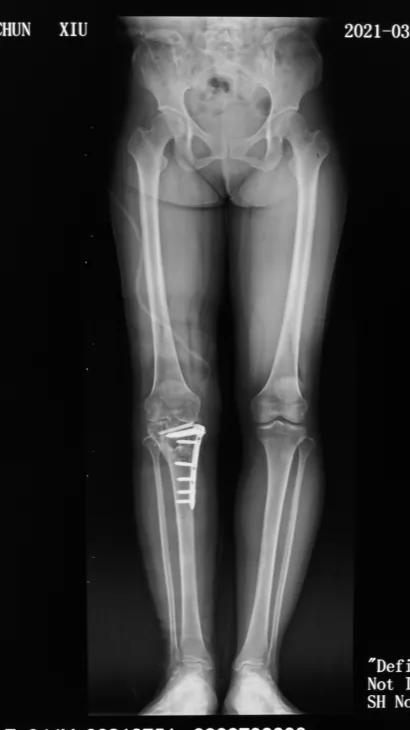

经过详细问诊以及X线检查,发现杨女士胫骨平台畸形愈合,平台大于股骨远端,膝关节对合不佳。刘万军主任决定行胫骨内侧髁截骨(TCVO),经过一系列周密的术前计划,刘主任为杨女士术前量身制作截骨模板,术后杨女士当天便可以下床活动,第二天就可以出院了,看见自己的腿由弯变直,杨女士的脸上露出了久违的笑容,对刘万军主任团队高超的医术赞不绝口。

术后

TCVO不仅可以矫正下肢力线,也能恢复关节面宽度,改善关节稳定性。减少外侧关节半脱位,负重重新分配到外侧间室,调整外侧间室间隙,改善关节内外翻的不稳性。

总之,胫骨高位截骨术是一个微创手术,仅在骨头上切开一道缝隙,再把截骨面以合适的角度撑开,并用接骨板固定,因此不会有骨头的移除,对于伴有膝内翻畸形的膝关节内侧关节面磨损患者是很好的手术选择。